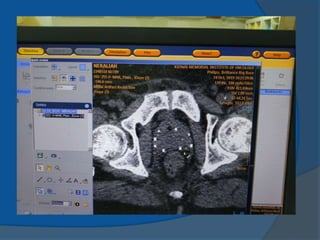

1983 Hans HenrikHolm use of transrectal ultrasound to visualize the permanent placement of I-125 seeds via needles inserted through the perineum directly into the prostate implanting I-125 seeds into cancerous prostates, under the direction of axial imaging from a rectal probe mounted on a sledge-stepper (stepping unit). 1985 Blasko and Ragde the first transperineal, ultrasound- guided approach in the United States ultrasound-guided approach resulted in increased accuracy of needle and seed placement and relatively even distribution of seeds throughout the prostate it allowed computerized treatment planning of the implant rather than the use of simple nomograms ensuring the proper number, strength, and positioning of radioactive sources.